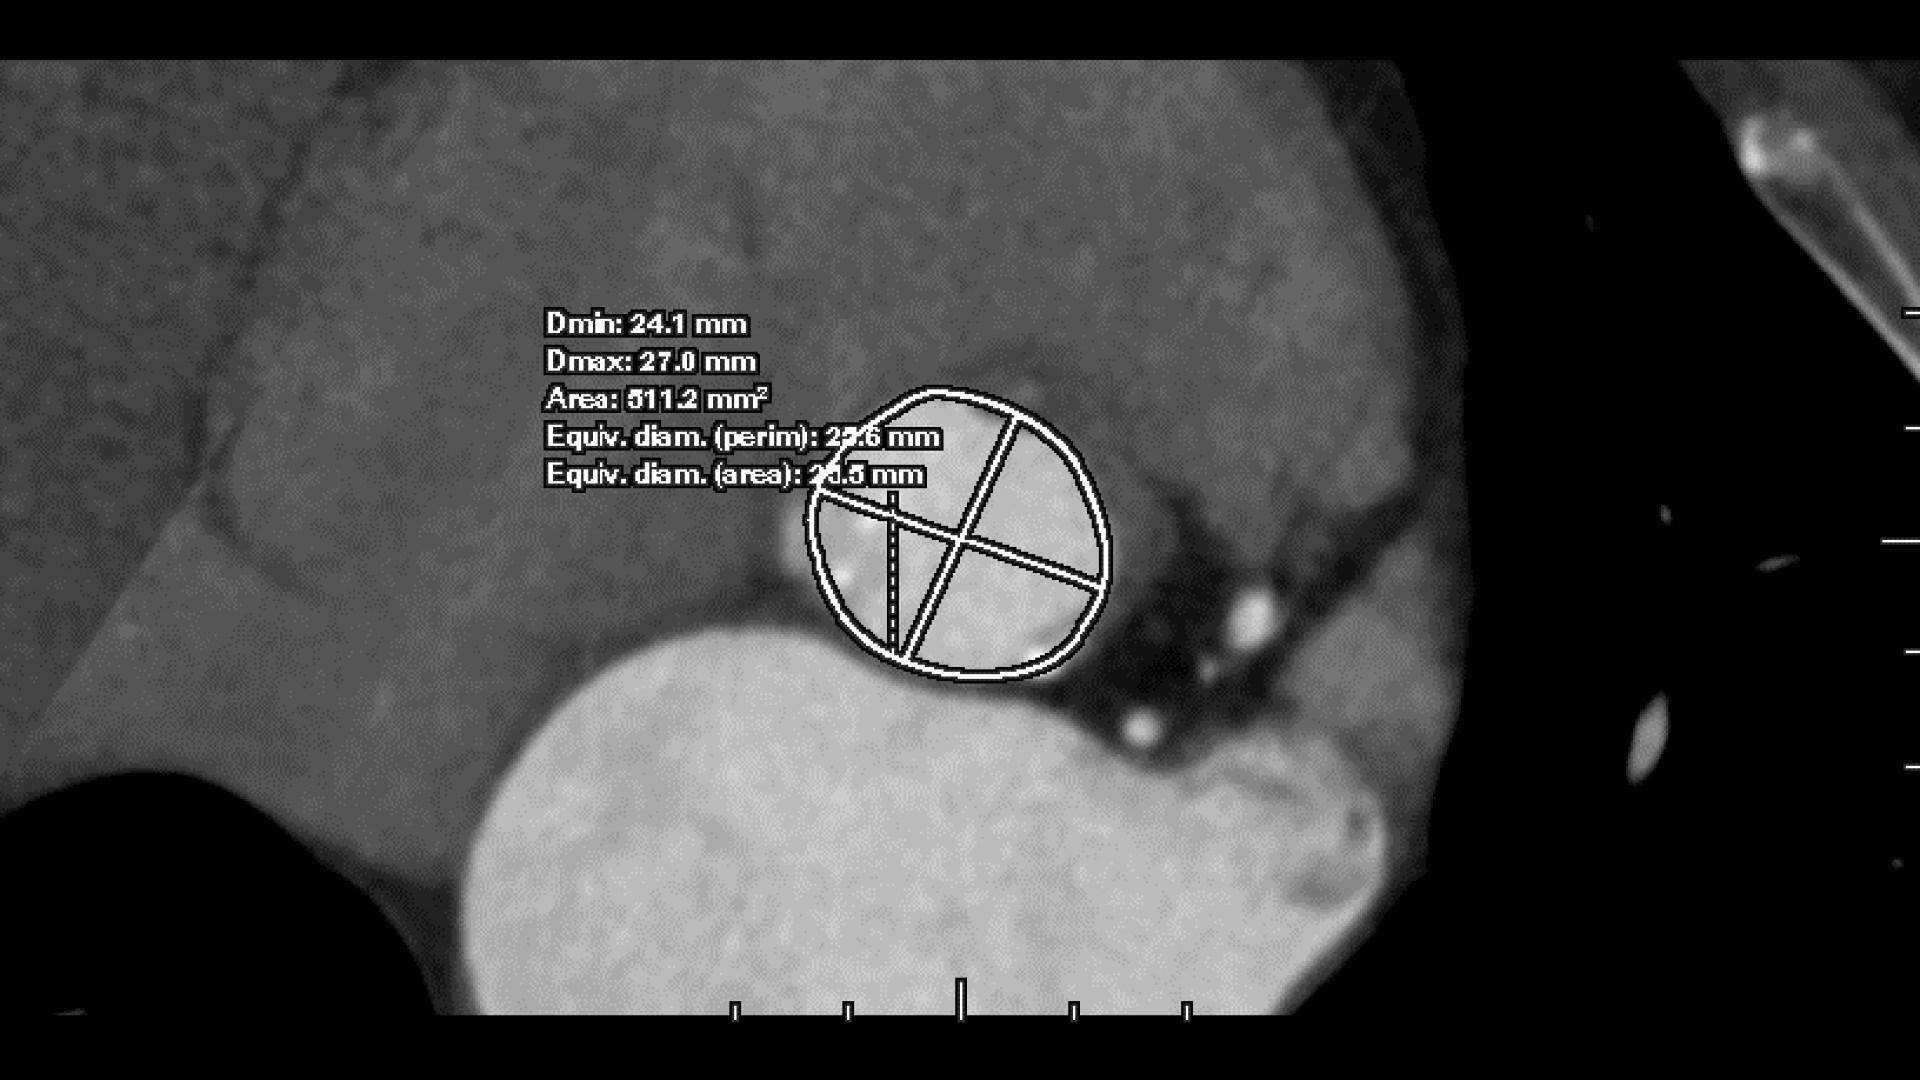

Faster annulus plane detection and aortic annulus measurements*

• 3-point deposit mode for precise refinement of annular plane

• >Faster valve plane detection over a manual method